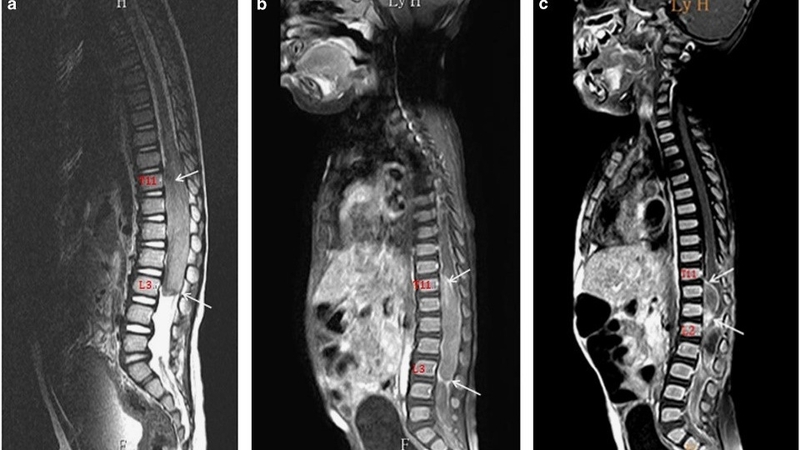

Kĩ thuật chụp cộng hưởng từ (MRI) đã lâu đã được biết đến như một phương pháp chẩn đoán hình ảnh tiên tiến và hiện đại, đặc trưng bởi tính không xâm lấn và giá trị chẩn đoán cao. Vậy đối với trẻ em, quá trình chụp cộng hưởng từ diễn ra như thế nào và liệu kỹ thuật này có tác động đến sức khỏe của trẻ không?

Phương pháp chụp cộng hưởng từ (MRI) là một kỹ thuật tạo hình cắt lớp thông qua sử dụng từ trường và sóng radio để tương tác với nguyên tử Hydrogen trong cơ thể. Nguyên tắc hoạt động này dựa trên việc các nguyên tử Hydrogen hấp thụ và sau đó phóng thích năng lượng sóng radio. Máy chụp MRI sẽ sau đó thu nhận, xử lý tín hiệu này và chuyển đổi chúng thành hình ảnh chất lượng cao.

Hình ảnh từ chụp MRI mang lại chi tiết giải phẫu tốt, độ tương phản cao và khả năng tái tạo 3D, mà không gây tác dụng phụ đáng kể. Đây là một kỹ thuật tiên tiến đang được rộng rãi áp dụng trong lĩnh vực chẩn đoán hình ảnh y tế. MRI không chỉ giúp xác định các bệnh lý mà còn có khả năng phát hiện những vấn đề phức tạp mà các phương pháp chụp hình khác như X-quang hay siêu âm không thể phát hiện ra được.